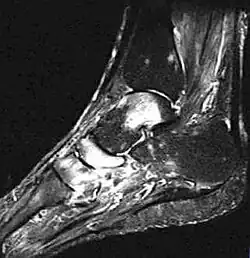

- Fuß, MRT, T2-Gewichtung

Zum Vergleich: Sprungbein, Kahnbein und Keilbein unauffällig